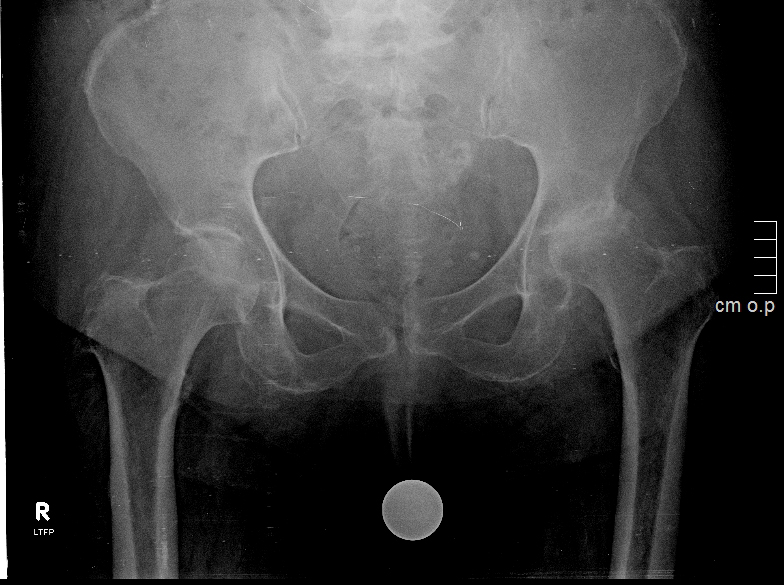

Η οστεοαρθρίτιδα ισχίου είναι μία εξαιρετικά κοινή πάθηση καθώς, σύμφωνα με το CDC, η πιθανότητα να αναπτύξουν συμπτωματική οστεοαρθρίτιδα κάποια στιγμή στη ζωή τους είναι 28,6% για τις γυναίκες και 18,5% για τους άνδρες. Πρόκειται για μια εκφυλιστική αρθρίτιδα που εκδηλώνεται με πόνο, χωλότητα και περιορισμό στο εύρος κίνησης, ενώ τα ακτινολογικά ευρήματα περιλαμβάνουν στένωση του μεσάρθριου διαστήματος, σκλήρυνση, υποχόνδριες κύστεις και παρουσία οστεόφυτων.